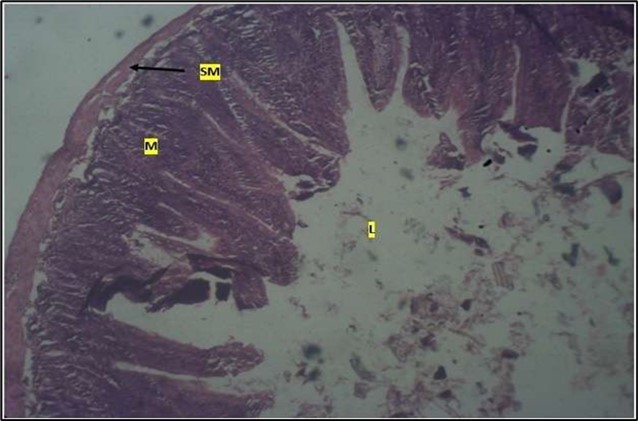

Histological examination of the small intestine result in control animals revealed a normal architecture with the red pulp and white pulp with no pathological observation Figure 2. Administration of Abelmoschus esculentus at low dose shows an increased cellularity with numerous cells in the Mucosa and the villi projecting towards the lumen. Focal metaplasia of mucosal cells alongside villous disruption was also observed (Figure 3). The high dose group showed normal cellular architecture with no villous disruption (Figure 4).

Figure 3.Low dose showing numerous epithelial cells in the mucosa (m) with villi projecting towards the lumen (l). The is focal metaplasia of the mucosal cells with villous disruption. smooth muscle layer appears normal. H & E. X40

Low dose showing numerous epithelial cells in the mucosa (m) with villi projecting towards the lumen (l). The is focal metaplasia of the mucosal cells with villous disruption. smooth muscle layer              appears normal.  H & E. X40